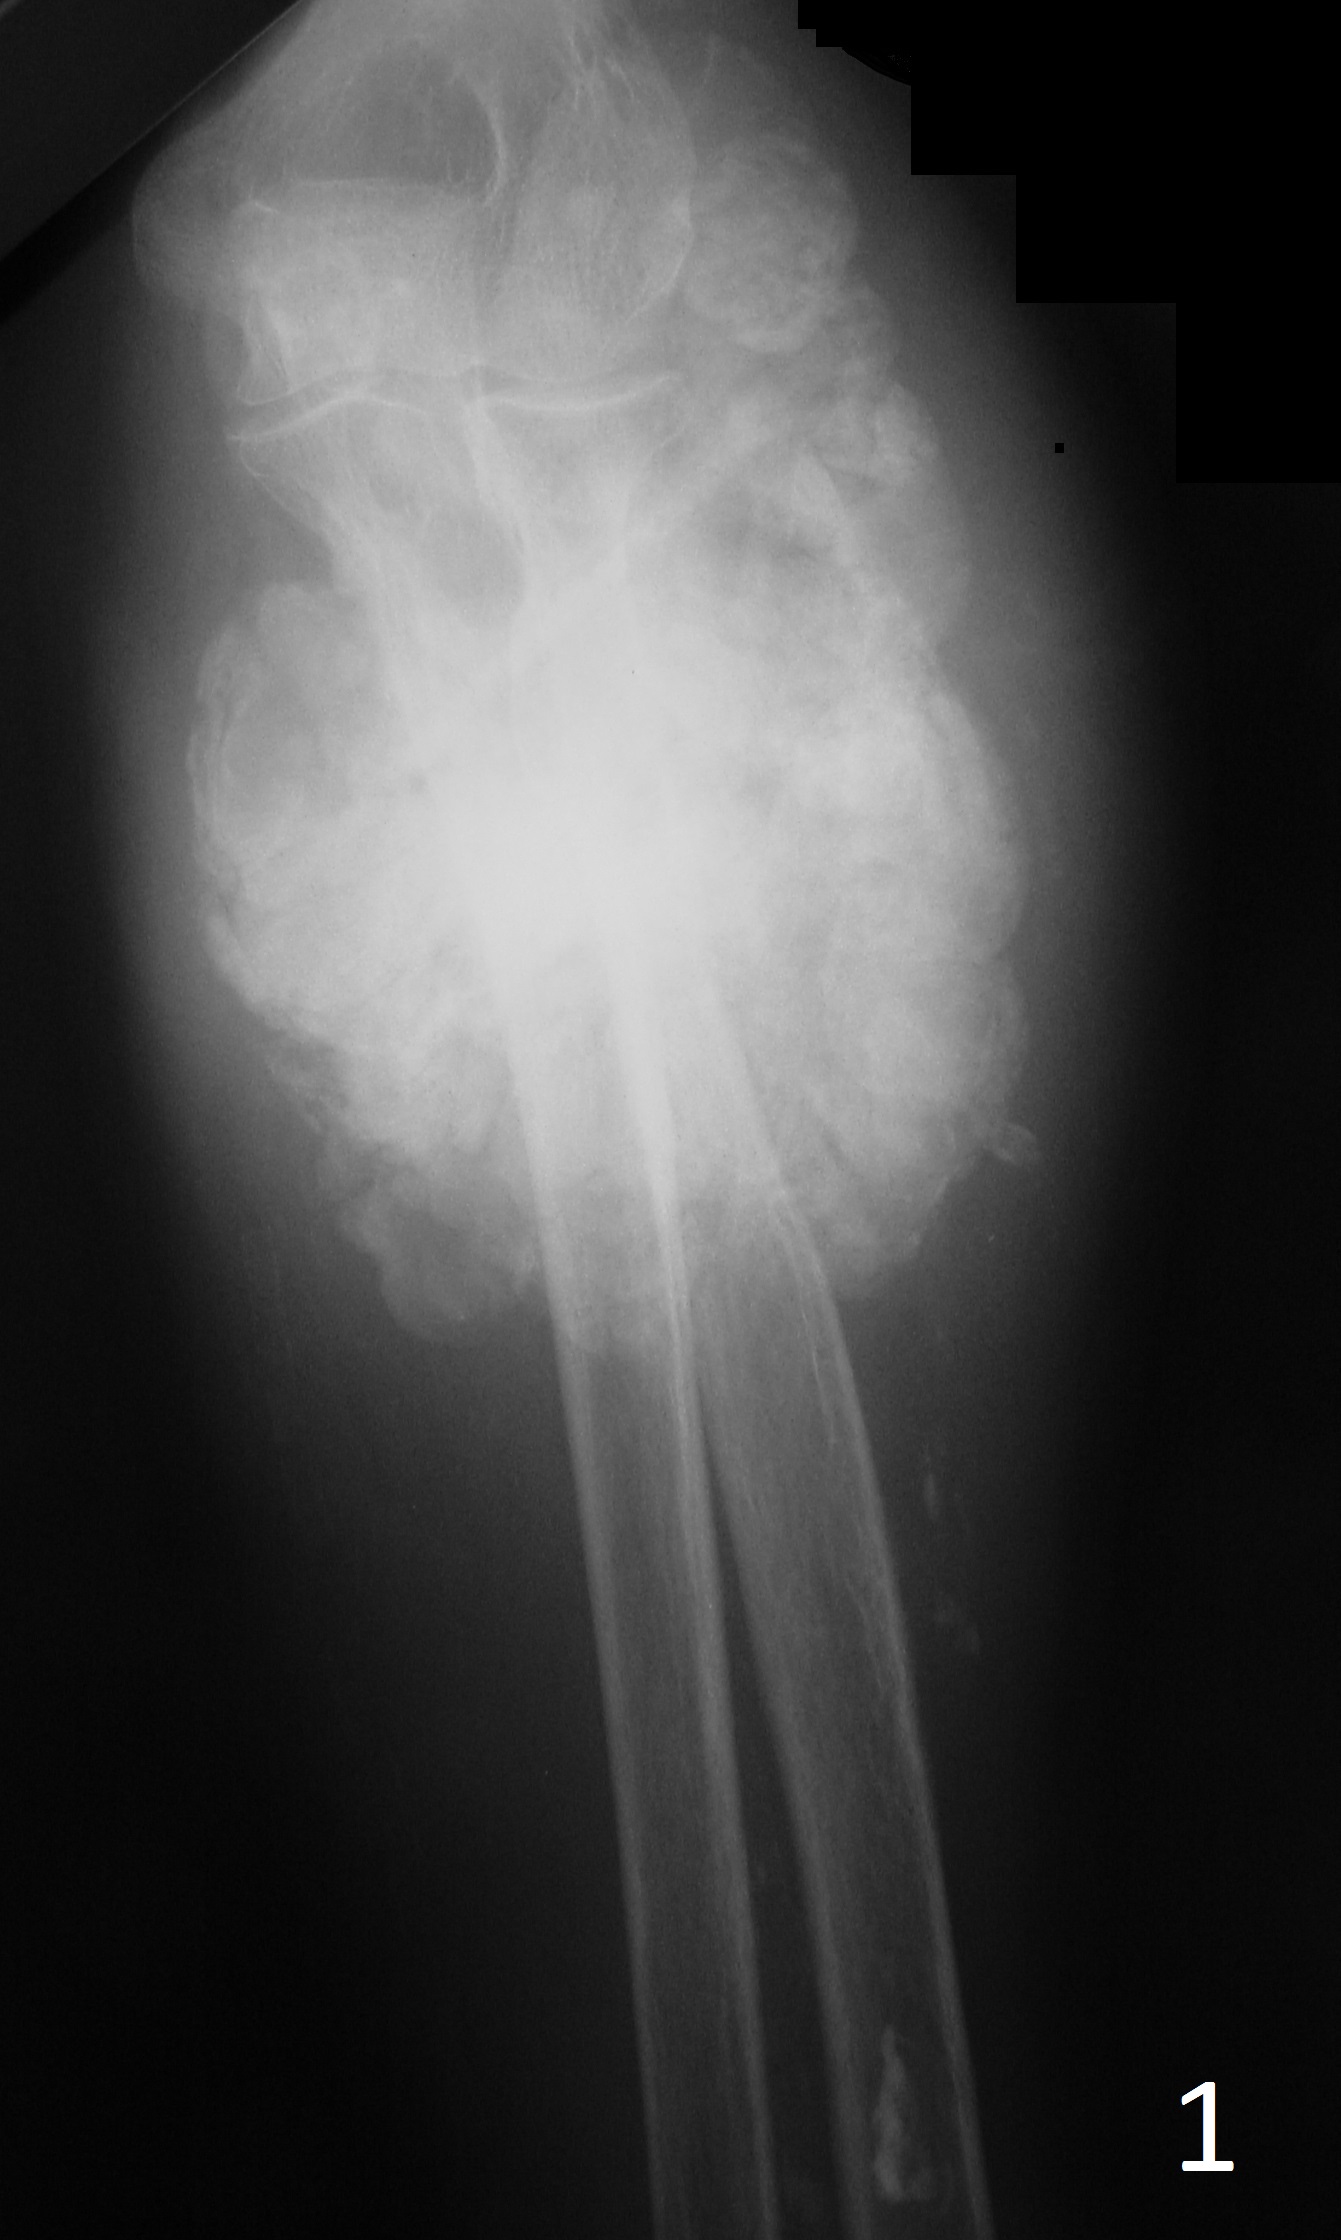

GENERAL INFORMATION Synovial sarcoma is a common soft tissue malignancy accounting for 5 – 10 % of soft tissue sarcomas. Patients with synovial cell sarcoma are often between the ages of 15 and 35 years old; generally younger than patients with other types of soft...